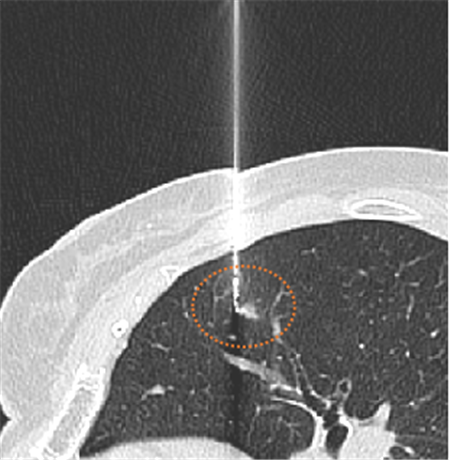

CT引导下肺小结节术前辅助定位就成为了有效的手段。在临床使用中安全可靠、成功率高、并发症少,可为临床医生在术中快速准确探寻结节位置、最大限度精准切除肿瘤,并给病理科医生提供精准的切片范围,不仅缩短了患者手术时间、降低手术风险,而且可较大限度保护患者肺组织、肺功能。目前,玉溪市人民医院已成功的进行了多例CT引导下肺结节穿刺术前定位,穿刺过程顺利,手术成功。

CT呈像浸润性腺癌引导定位